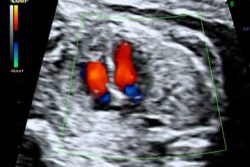

Contamos con alta tecnología, ecógrafo de alta gama para realizar ecografía 3D, 4D, 5D y 6D o SILHOUETTE lo que permite ver los detalles y evaluar los embarazos de alto riesgo en búsqueda de alteraciones anatómicas o funcionales del feto.